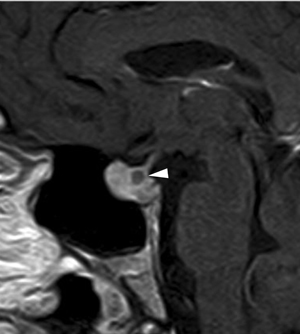

A diferencia de la tomografia computada, que emplea tubos de rayos X, la RM no utiliza radiaciones ionizantes, lo que es una ventaja a considerar en los pacientes pediátricos y en las mujeres embarazadas. La RM tiene una excelente resolución espacial y de tejidos blandos; por ejemplo permite precisar la presencia o ausencia de la neurohipófisis, lo que no es posible con la Tomografia Computada5-7. Con la TAC, con o sin medio de contraste yodado, es posible detectar microadenomas y macroadenomas pituitarios (Figuras 1A y 1B); sin embargo, en los macroadenomas puede ser difícil distinguir las relaciones del tumor con el quiasma óptico, o definir la invasión del seno cavernoso. Además, los artefactos producidos por amalgamas dentales deterioran las imágenes y la dificultad para lograr posiciones cómodas para los pacientes, con el fin de obtener cortes coronales directos, limitan la utilidad de la TAC.

En todo caso si la RM no está disponible o está contraindicada, por ejemplo en un paciente con un marcapaso cardíaco, la TAC con equipos de multicorte puede ser suficiente en la evaluación de microadenomas, teniendo presente que en estos tumores milimétricos la TAC tiene un 25% de falsos negativos; así, en estos casos los antecedentes clínicos y los exámenes de laboratorio son fundamentales8,9.

En los tumores grandes (macroadenomas) la TAC puede entregar información diagnóstica adecuada, pero no supera la definición que se logra con equipos de RM superconductores (Figuras 2 A y 2B).

Figura 1A y B. TAC con contraste yodado, corte coronal, muestra un microadenoma lateralizado a izquierda (punta de flecha). Control a los 2 años. TAC con contraste yodado, corte coronal, demuestra aumento de volumen del microadenoma, lo que es infrecuente de observar en clínica (punta de flecha).

Figura 2A y B. Cortes sagitales de RM y TAC. Adenoma pituitario con invasión del esfenoides y del clivus (puntas de flecha). Es posible demostrar las estructuras óseas en RM con similar precisión que la TAC.